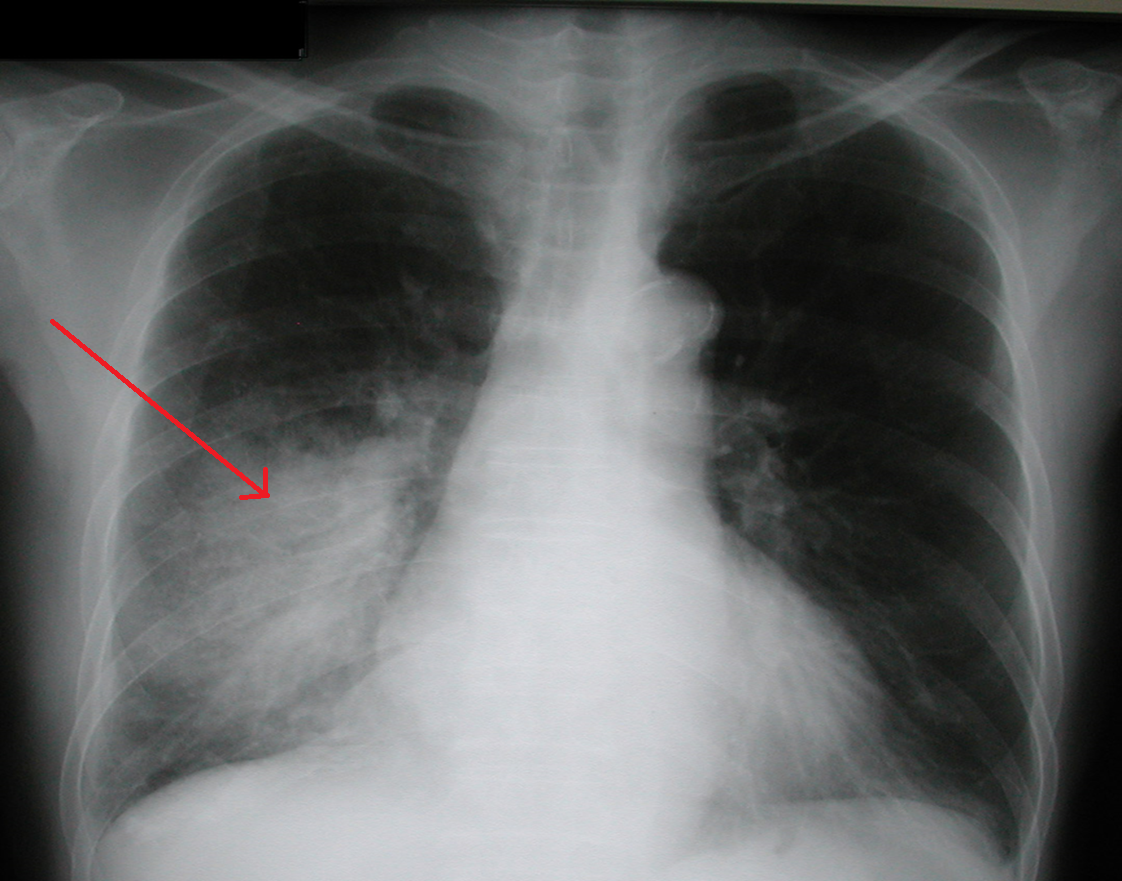

Kā sauc attēlā redzamo dzīvībai bīstamo patoloģiju?

0%

100%

RTG attēlā redzams pneimonijas attēls – plaušu iekaisums labajā apakšdaivā. Kādi trokšņi visbiežāk auskultējami virs šāda iekaisuma?